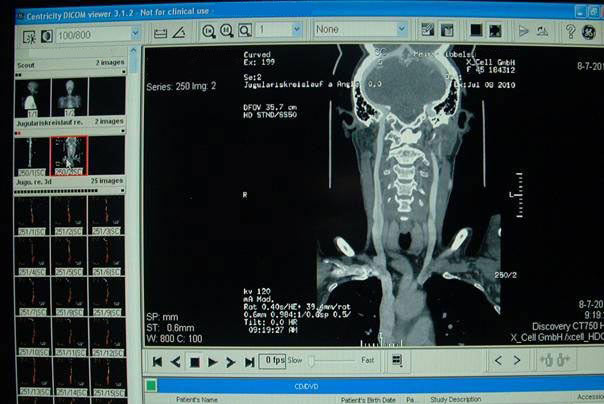

Het onderzoeken naar Chronsiche Cerebro Spinale Veneuze Insuffiëntie (CCSVI) worden

op basis van zgn. protocollen van Dr. Zamboni worden uitgevoerd.

Bestaat uit een MRV onderzoek Echografie / doppler / duplex (hoofd-, hals-, thoraxveins)

en een CT scan.

ging Annet gelijk door voor een CT-scan, dit duurde ongeveer een kwartiertje.

Na goed een half uur kregen we het nagesprek met Dokter Kraus hij bevestigde dat

Annet twee vernauwingen heeft een die links erg dicht zit en de ander aan de rechter

kant die al lekker op begon te schieten dus die moet dan ook gedaan worden.

Na uitleg van de foto’s kregen we diezelfde foto’s op een Cd-rom mee ook heeft hij

uitgelegd wat er gaat gebeuren.

Via de lies gaat eer een soort van slangetje naar de dichtgeslipte aders en daar

aangekomen word er een soort van ballontje op geblazen en op die mannier de aders

opgerekt zodat het bloed weer de juiste kant op kan.

Hieronder enkele foto’s van de vernauwing.